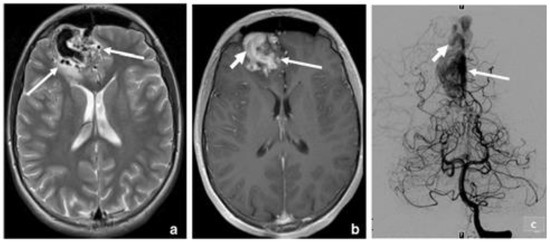

3.2. Arteriovenous Malformation (AV Angioma, Cirsoid Angioma)

- Faye, M.; Diallo, M.; Sghiouar, M.; Ndiaye Sy, E.C.; Borius, P.Y.; Régis, J.-M. Stereotactic Radiosurgery for Thalamus Arteriovenous Malformations. J. Radiosurg. SBRT 2020, 6, 269–275. [Google Scholar] [PubMed]

- Healy, V.; O’Halloran, P.J.; Husien, M.B.; Bolger, C.; Farrell, M. Intermixed Arteriovenous Malformation and Hemangioblastoma: Case Report and Literature Review. CNS Oncol. 2020, 9, CNS66. [Google Scholar] [CrossRef] [PubMed]

- Sabayan, B.; Lineback, C.; Viswanathan, A.; Leslie-Mazwi, T.M.; Shaibani, A. Central Nervous System Vascular Malformations: A Clinical Review. Ann. Clin. Transl. Neurol. 2021, 8, 504–522. [Google Scholar] [CrossRef] [PubMed]

- Goyal, P.; Mangla, R.; Gupta, S.; Malhotra, A.; Almast, J.; Sapire, J.; Kolar, B. Pediatric Congenital Cerebrovascular Anomalies: Congenital Cerebrovascular Anomalies. J. Neuroimaging 2019, 29, 165–181. [Google Scholar] [CrossRef] [PubMed]

- Rodrigues de Oliveira, L.F.; de Castro-Afonso, L.H.; de Freitas, R.K.; Colli, B.O.; Abud, D.G. De Novo Intracranial Arteriovenous Malformation—Case Report and Literature Review. World Neurosurg. 2020, 138, 349–351. [Google Scholar] [CrossRef]

- Guizado Infante, V.M.; Mejía Maggi, N.C.; Carrera Silva, D.M. Malformación Arteriovenosa Cerebelosa. Caso Clínico. Eugenio Espejo 2019, 13, 71–78. [Google Scholar]

- Kassiri, J.; Rajapakse, T.; Wheatley, M.; Sinclair, D.B. Neurovascular Lesions in Pediatric Epilepsy. J. Child. Neurol. 2019, 34, 549–555. [Google Scholar] [CrossRef]